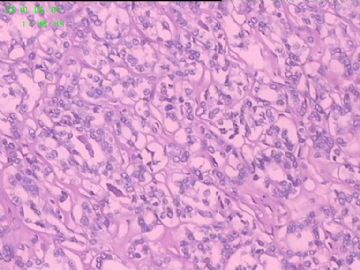

灰白结节2枚,其一2.5x1.8x1.5cm,包膜完整,内为褐色胶质,其二3x2.5x1.5cm包膜完整,切面灰白实性。附件镜下为后者。

可能楼主看到那些核的变化吧?但是没有其他支持的条件,还是应该是结甲。

就这几幅图似乎不够说明问题,细胞有一定的异型性,但是,最好能采到交界处的情况再判断。癌与非癌,最好能有组织结构与细胞异型性结合来看。

有些核透明,无其它特点,恶性证据是没有。